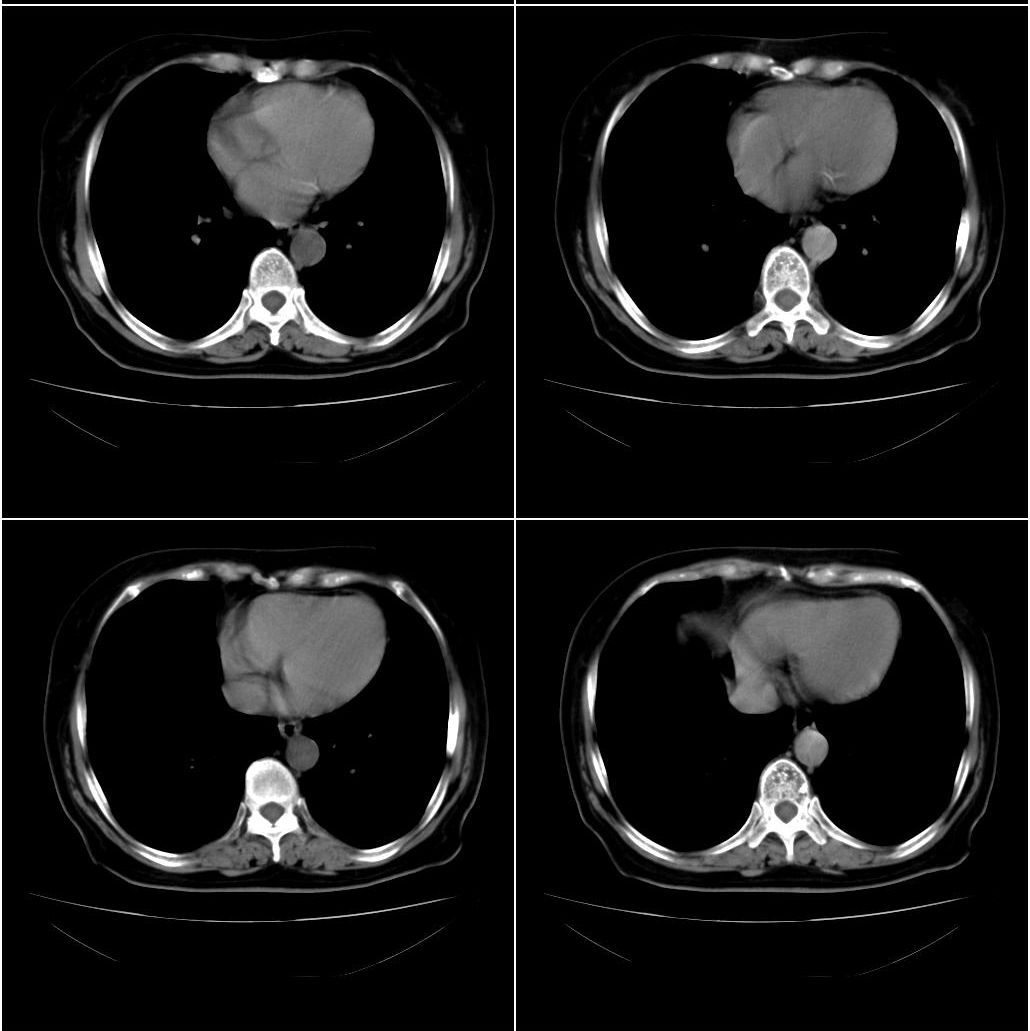

以下是引用zhangxu5888在2007-12-22 20:56:00的发言:[br]食道病变???纵隔淋巴瘤?

以下是引用卜一在2007-12-22 22:44:00的发言:[br]纵隔占位,支持:气管源性肿瘤!

以下是引用sxlcbc在2007-12-23 4:27:00的发言:[br]气管源性肿瘤觉得有点不靠谱啊,看上去气管是受压改变的。更像是上段食管的改变,周围淋巴结肿大,食管受压。看看以下六幅图片:[br]不过,有一点不好理解:食管肿瘤应该有食道症状的,再说食管癌出现周围这么大的淋巴结也不多见啊,如果考虑淋巴瘤倒是更合理一点,这样气管,食管受压改变也许更合理一些。[br][br]